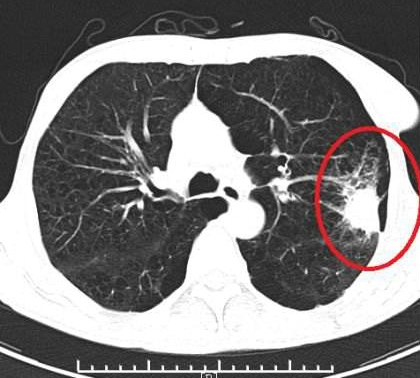

在結腸鏡插鏡到盲腸時,內鏡醫(yī)師留取圖像,此時智能輔助系統(tǒng)自動啟動,伴隨著腸鏡醫(yī)師的退鏡一起實時監(jiān)督腸道內有無息肉或病變的出現(xiàn)。當人工智能系統(tǒng)懷疑有病變在腸道內出現(xiàn)時,會實時地發(fā)出警報聲音提醒腸鏡醫(yī)生注意可能遺漏的病變,并且會實時的標注出系統(tǒng)高度懷疑有病變的部位,幫助內鏡醫(yī)生發(fā)現(xiàn)更多有潛在危險性的病變,做到結直腸癌的早預防、早發(fā)現(xiàn)和早治療。